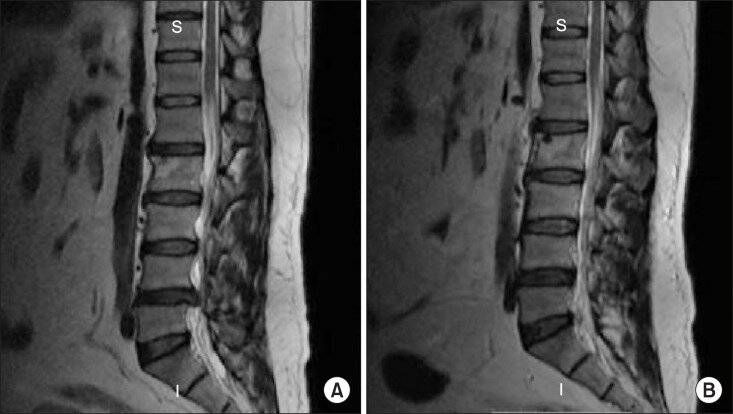

МРТ пациента, сагиттальные изображения МРТ пациента, который сообщил о выздоровлении через 7 месяцев после лечения.

Анализ данных показал, что медикаментозное лечение и адекватный покой могут быть многообещающим терапевтическим вариантом в отдельных случаях грыжи межпозвонкового диска, не имеющих абсолютных показаний к экстренному хирургическому вмешательству.